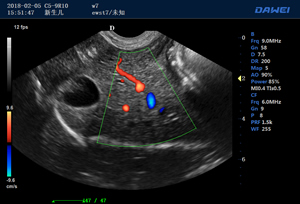

便攜式獸用b超機-彩色多普勒動物超聲診斷儀

S80高端便攜獸用彩超-彩色多普勒多普勒超聲診斷儀

·支持B、C、PW、CW、寬景成像

適用于各種動物的臨床腹部、胸腔,心臟、肌腱、小器官、眼球、生殖系統等的檢查

S80高端便攜獸用彩超-彩色多普勒多普勒超聲診斷儀掃描圖 S80高端便攜獸用彩超-彩色多普勒多普勒超聲診斷儀 S80高端便攜獸用彩超-彩色多普勒多普勒超聲診斷儀